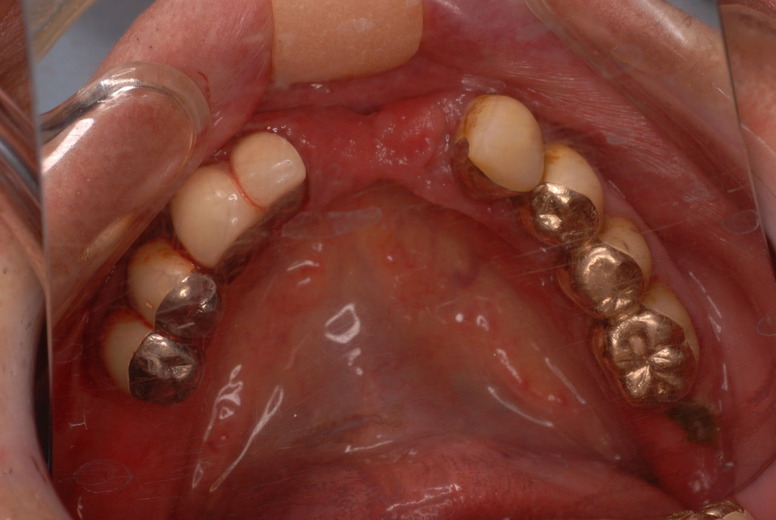

下の歯は数本存在しますが、全て虫歯と歯周病に犯されていました。

食べカスまみれで歯周病に罹患しています。